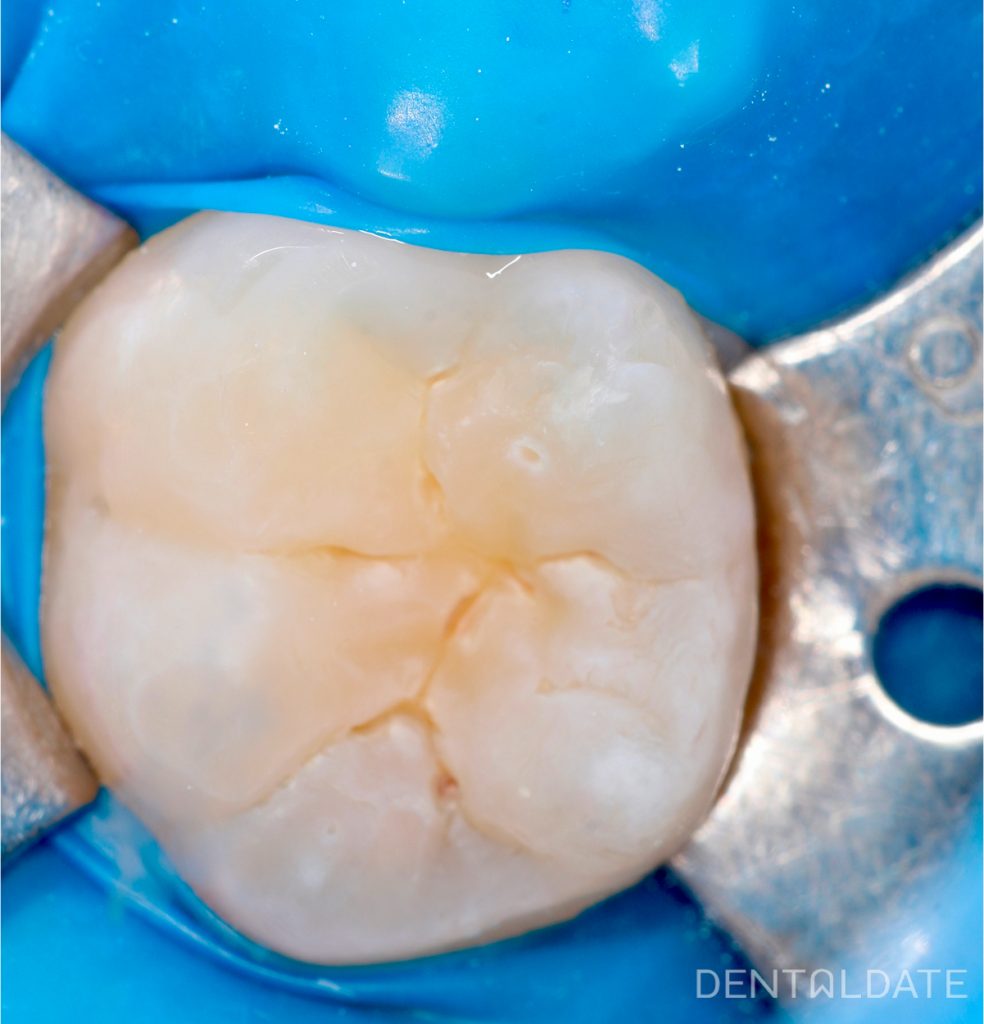

Clinical findings: Tooth 3.6 is partially erupted with deep fissures, no signs of demineralization or caries. The tooth is vital, normal response to cold stimulus.

Treatment: Pit and fissure sealing was performed using the following steps:

- Cleaning and drying of the occlusal surface

- Etching the enamel (with 35–37% phosphoric acid)

- Rinsing and drying

- Application of light-curing sealant

- Light curing and occlusal adjustment